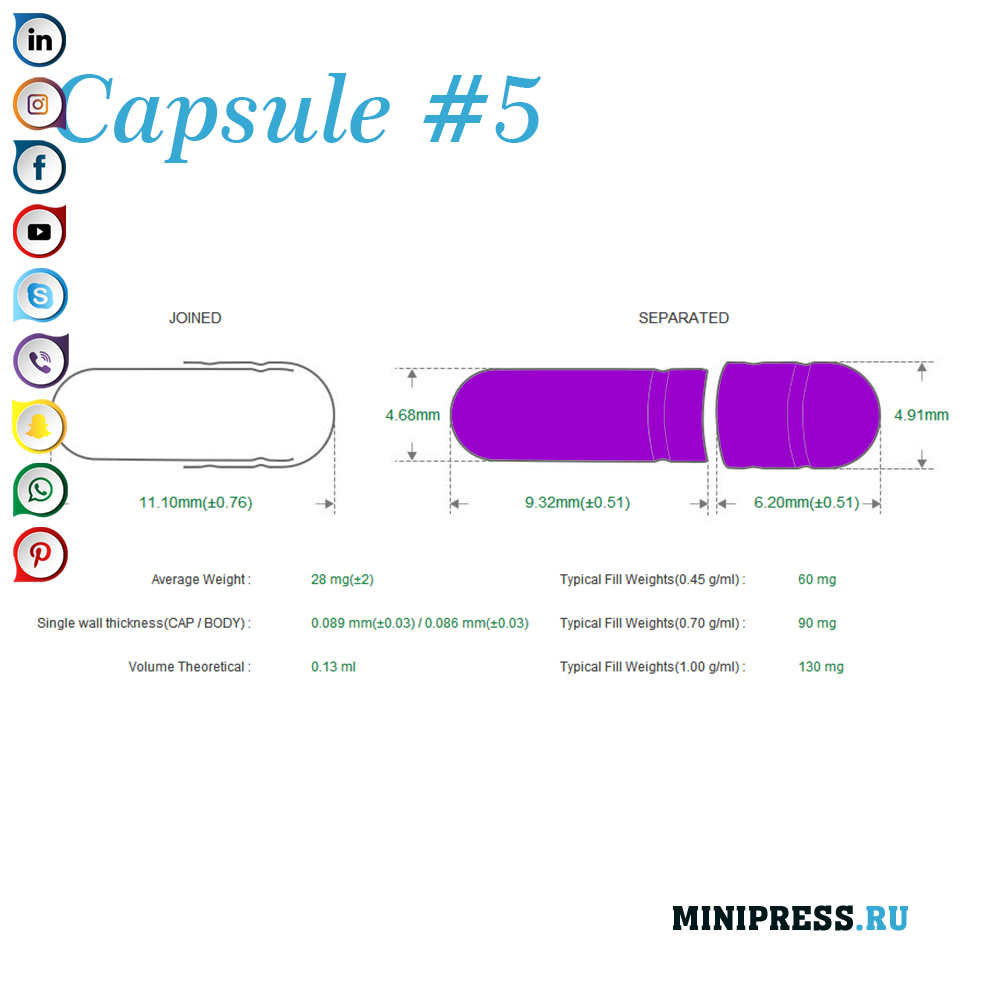

Velike zelatinskih kapsula: 000,00,0,1,2,3,4,5, A, B, C, D, E.